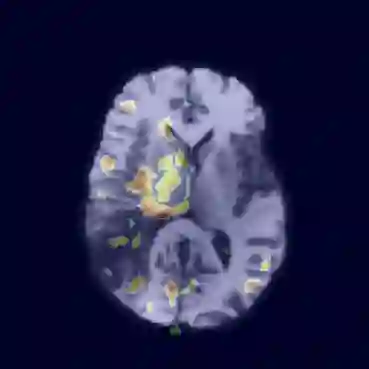

Unsupervised Anomaly Detection has become a popular method to detect pathologies in medical images as it does not require supervision or labels for training. Most commonly, the anomaly detection model generates a "normal" version of an input image, and the pixel-wise $l^p$-difference of the two is used to localize anomalies. However, large residuals often occur due to imperfect reconstruction of the complex anatomical structures present in most medical images. This method also fails to detect anomalies that are not characterized by large intensity differences to the surrounding tissue. We propose to tackle this problem using a feature-mapping function that transforms the input intensity images into a space with multiple channels where anomalies can be detected along different discriminative feature maps extracted from the original image. We then train an Autoencoder model in this space using structural similarity loss that does not only consider differences in intensity but also in contrast and structure. Our method significantly increases performance on two medical data sets for brain MRI. Code and experiments are available at https://github.com/FeliMe/feature-autoencoder

翻译:通常,异常检测模型产生输入图像的“正常”版本,而两者的像素-WY $l ⁇ p$-difference被用来将异常现象本地化。然而,由于大多数医学图像中存在的复杂的解剖结构的重建不完善,大量残留物往往出现。这种方法也未能检测出与周围组织没有严重强度差异特征的异常现象。我们提议使用地貌图功能来解决这个问题,将输入强度图像转换成一个有多种频道的空间,在从原始图像中提取的不同歧视性特征地图中可以检测出异常现象。我们然后在这个空间中培训一个自动编码模型,使用的结构相似性损失不仅考虑到强度差异,而且还考虑到对比和结构。我们的方法大大提高了大脑MRI两个医学数据集的性能。我们的方法和实验可在 https://github.com/FeliME/featriat-autoencoder 上查阅。